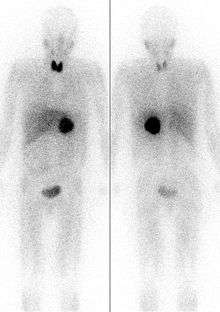

Thyroid iodine uptake blockade with potassium iodide is used in nuclear medicine scintigraphy and therapy with some radioiodinated compounds that are not targeted to the thyroid, such as iobenguane (MIBG), which is used to image or treat neural tissue tumors, or iodinated fibrinogen, which is used in fibrinogen scans to investigate clotting. These compounds contain iodine, but not in the iodide form. However, since they may be ultimately metabolized or break down to radioactive iodide, it is common to administer non-radioactive potassium iodide to ensure that iodide from these radiopharmaceuticals is not sequestered by the normal affinity of the thryoid for iodide.